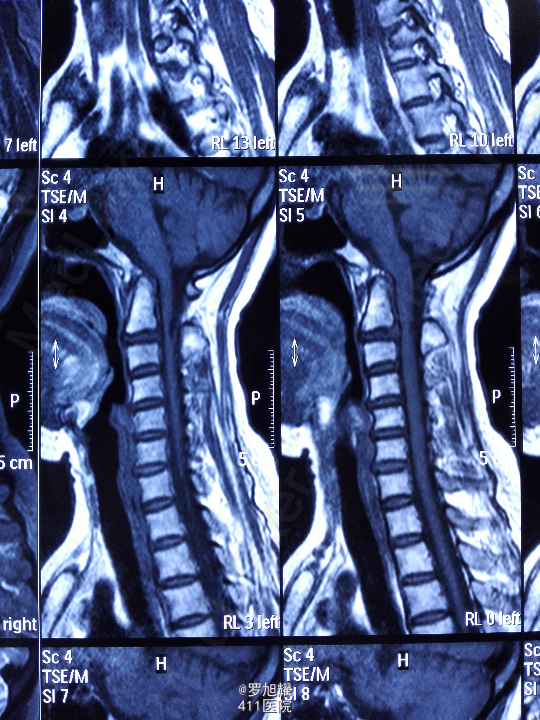

右侧躯体麻木1年,右上肢及下肢麻木2月余。 查体:颈椎活动受限,右上肢肘关节以远痛温觉减退,右侧胸4平面以下痛温觉及触觉减退,四肢肌力尚可,右侧霍夫曼征阳性,右侧上下肢所有腱反射亢进。 颈椎X线示:颈2椎板棘突缺如,颈3棘突肥大增高。 颈椎CT示:颈2椎板棘突缺如,颈3棘突肥大增高,颈2/3椎间盘突出,左侧颈2残留部分椎板进入椎管。枢椎齿突增生,寰枢关节退变。 颈椎MRI示:颈2/3椎间盘突出,左侧颈2椎板进入椎管,颈髓受压变性。

查体:颈椎活动受限,右上肢肘关节以远痛温觉减退,右侧胸4平面以下痛温觉及触觉减退,四肢肌力尚可,右侧霍夫曼征阳性,右侧上下肢所有腱反射亢进。 颈椎X线示:颈2椎板棘突缺如,颈3棘突肥大增高。 颈椎CT示:颈2椎板棘突缺如,颈3棘突肥大增高,颈2/3椎间盘突出,左侧颈2残留部分椎板进入椎管。枢椎齿突增生,寰枢关节退变。 颈椎MRI示:颈2/3椎间盘突出,左侧颈2椎板进入椎管,颈髓受压变性。